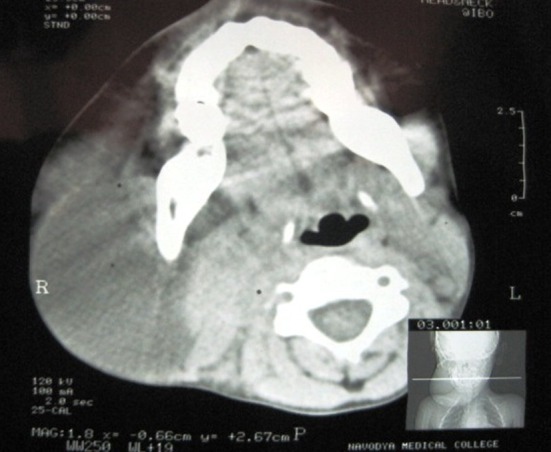

Fig. 2.

CT scan axial view showing the cystic lesion and its boundaries

A 6 year old male patient was referred to the department of oral and maxillofacial surgery with a chief complaint of large swelling on the right side of the jaw for past 2 years. Examination of the patient revealed soft, diffuse, mobile large swelling over the submandibular region (Fig. 1a, b). Swelling was small in size initially which gradually increased in size. The swelling was 12×8 cm in size non-tender, mobile, non-pulsatile, cystic in consistency, non-compressible and fluctulant. Transillumination test was positive and aspiration of the lesion resulted in brownish fluid. Clinical diagnosis of cystic hygroma was made. CT scan showed the extent of the tumor and showed large cystic lesion with definite boundaries (Fig. 2). The patient was then admitted for surgical removal of the lesion under general anesthesia. Through a submandibular incision, the lesion was completely excised (Figs. 3, 4). The facial nerve branches were identified and preserved. Careful dissection of the lesion anteriorly up to the midline, superiorly up to the lower border of the mandible, and posteriorly up to the tail of the parotid was carried out. The masses were separated from their attachment to sternocleidomastoid muscle. Hemostasis was achieved using cautery and ligation. Wound closure was done, by suturing the subcutaneous tissue followed by fascia and skin. The patient was hospitalized for 3 days and was discharged in a satisfactory condition (Fig. 5). There was no facial nerve deficit and patient is under regular follow up. The surgical specimen measured 7 × 5 cm, appeared irregular in shape but was well circumscribed. Cut surface revealed multiple cyst like spaces separated by thin fibrous septae and filled with gelatinous material and few cystic spaces filled with blood (Fig. 4). Histopathology revealed varying proportions of large and small lymphatic channels containing lymph, few blood vessels, adipose tissue, fibrous tissue, and lymphoid tissue. Areas of haemorrhage were also seen (Fig. 6). Based on the microscopic observations in correlation with clinical features, a final diagnosis of cystic hygroma was made.